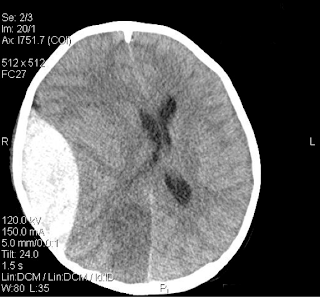

Στην Υπολογιστική Τομογραφία εγκεφάλου

εμφανίζεται ως υπέρπυκνη (hyperdense), αμφίκοιλου

(biconvex) σχήματος βλάβη.

Στην Υπολογιστική Τομογραφία εγκεφάλου εμφανίζεται ως υπέρπυκνη (hyperdense)

βλάβη σε σχήμα μηνίσκου (crescent – shape).

εμφανίζεται ως υπόπυκνη (hypodense) βλάβη σε

σχήμα μηνίσκου (crescent – shape).